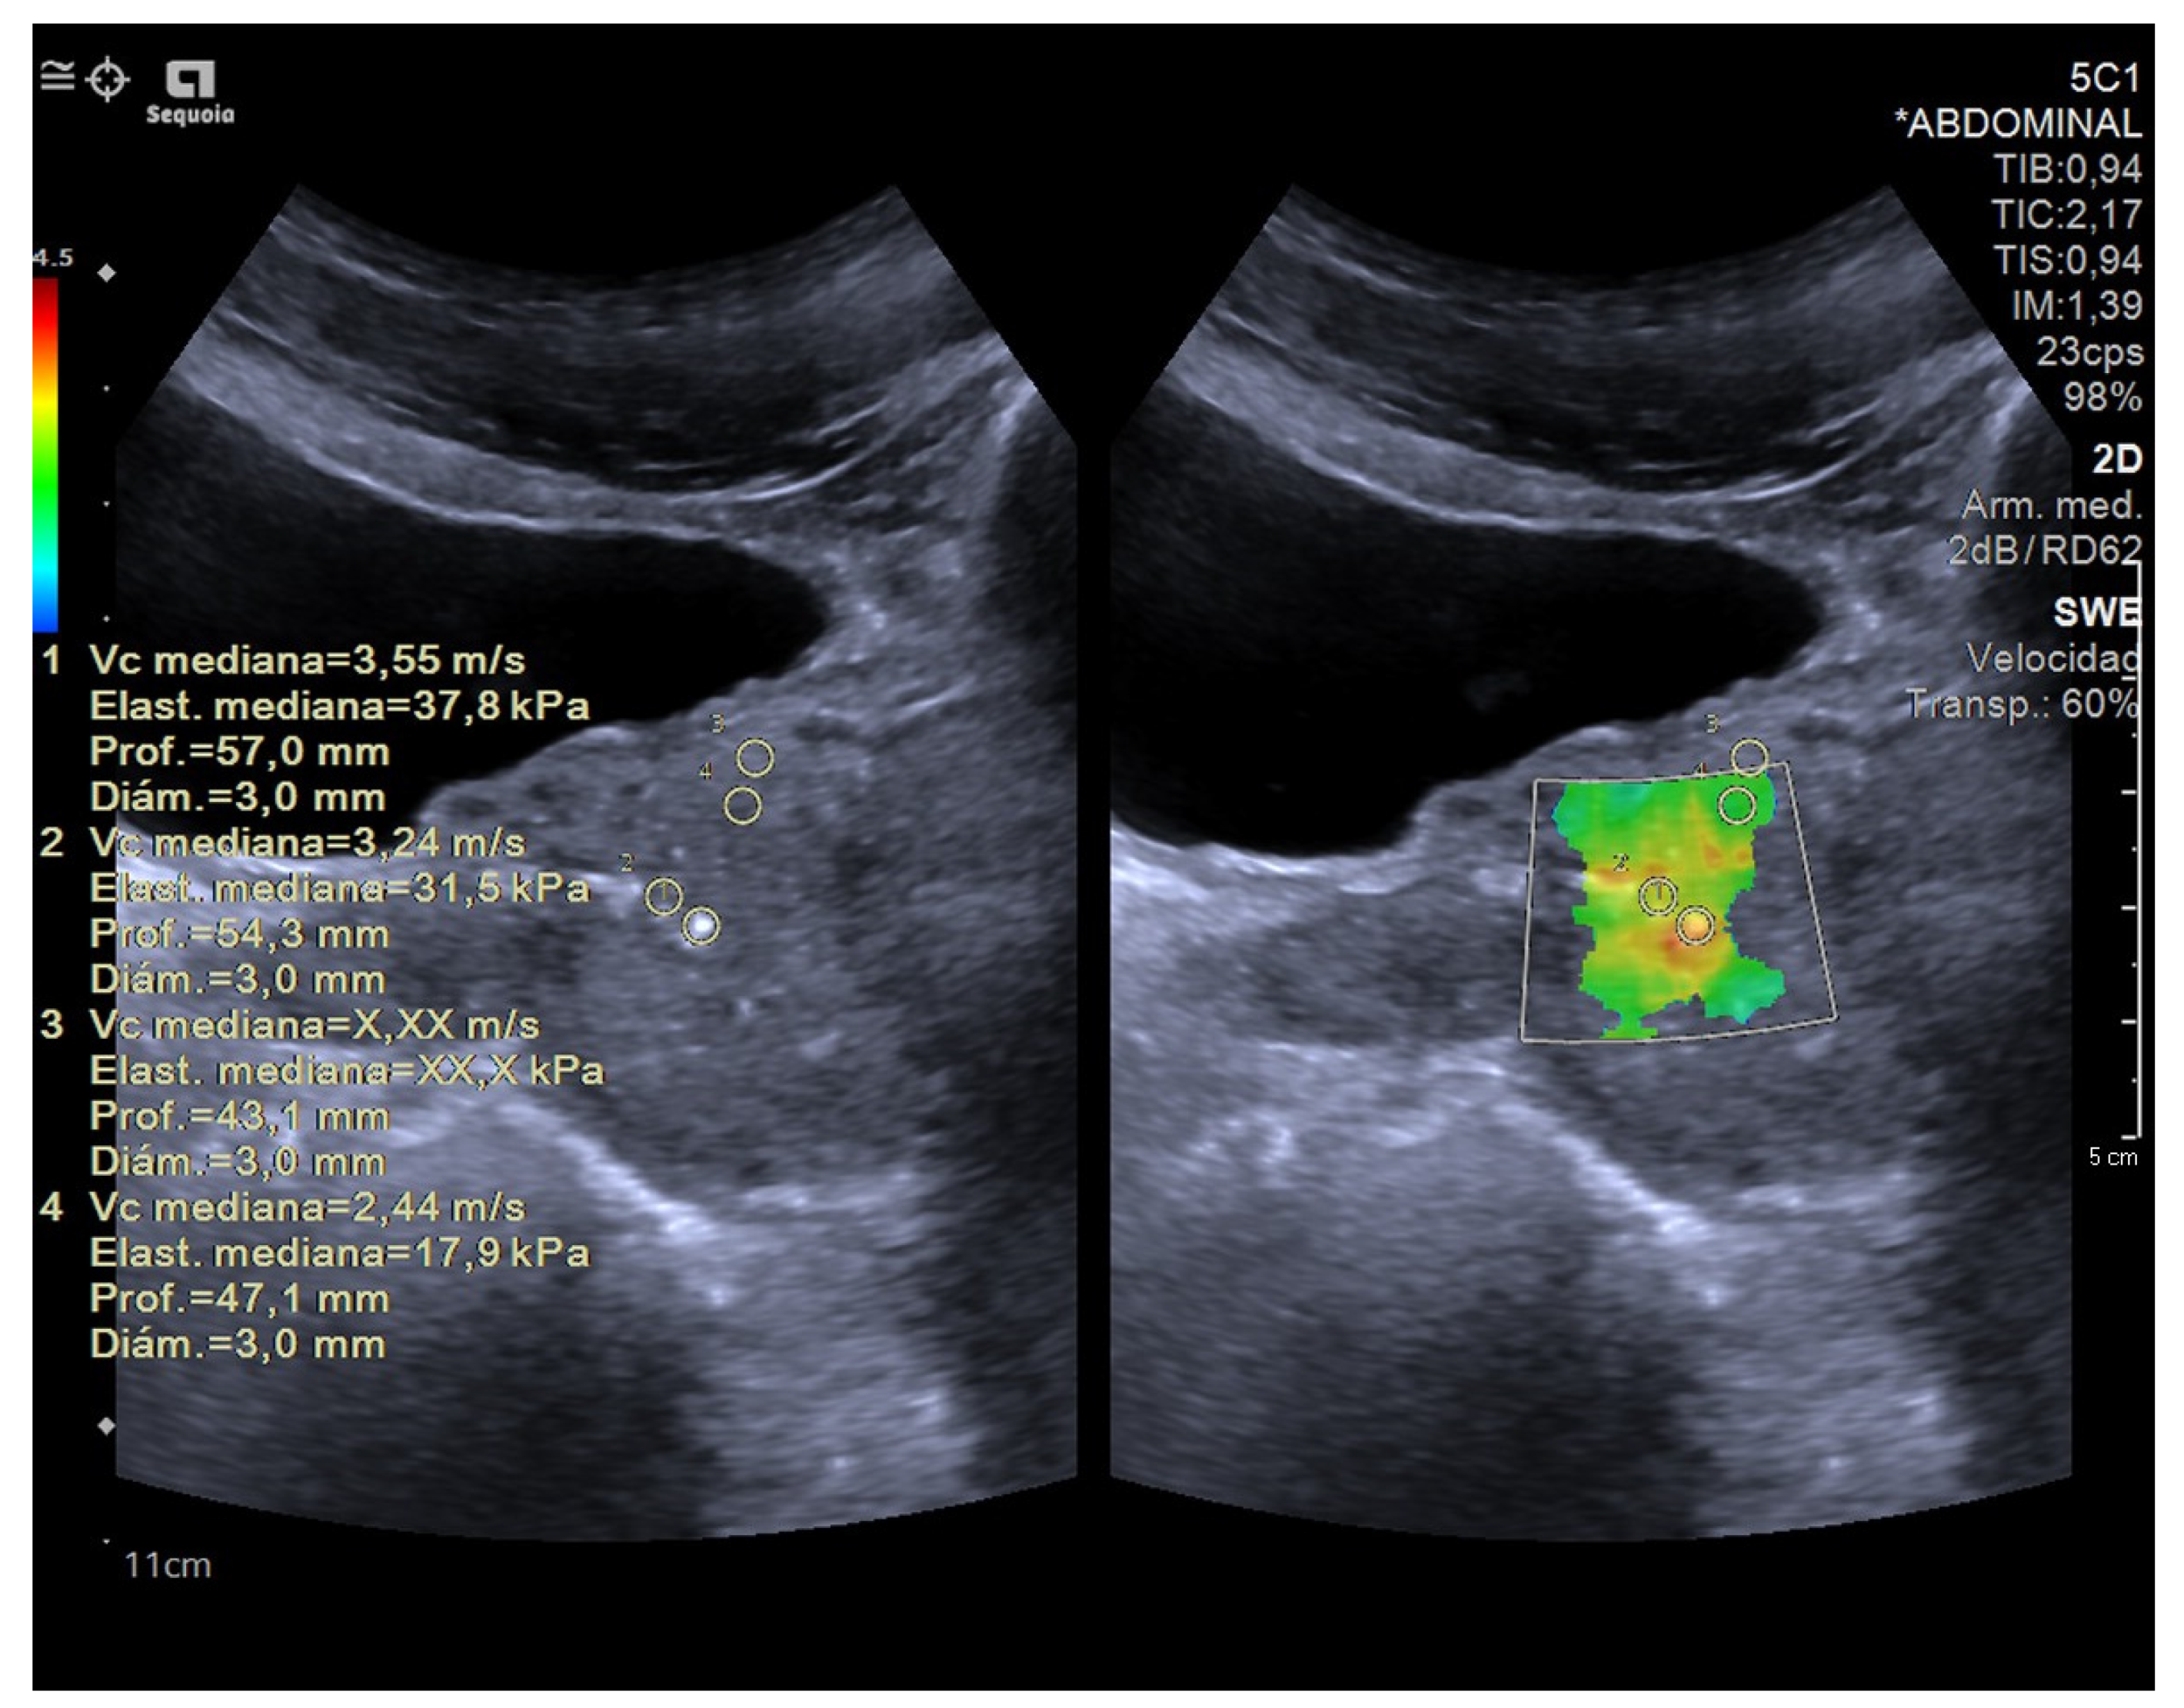

SE was interpreted based on the colour of the area in the elastography map. On the other hand, SWE was interpreted using a cut-off value in kilopascals. The SWE stiffness values in our study were based on transverse (axial) plane imaging (Figure 4 and Figure 5).

Figure 5.

41 year-old patient with elevated PSA without other clinical data of interest. Prostate ultrasound image with a suprapubic approach performed using a SIEMENS Sequoia ultrasound device with a Convex 5C1 probe. The elasticities of the tissues observed in the ROIs were 37.8 kPa in ROI 1; 31.5 kPa in ROI 2 and 17.9 kPa in ROI 4; ruling out the absence of malignant disease. Adjacent to the prostate, a hypoechoic area was identified, corresponding to an abscess, with the diagnosis being prostatitis. The absence of data indicating tissue stiffness in ROI 3 may be due to the heterogeneity of the sample.

According to the World Federation for Ultrasound in Medicine and Biology guidelines, for SWE, stiffness values >35 kPa (Young’s modulus) are interpreted as being suggestive of prostate cancer [39]. Recently, prostate biopsy guided with elastosonography has become an alternative to conventional ultrasound-guided systematic biopsy, showing a 50% reduction in the number of biopsy cores required using elastography [38].